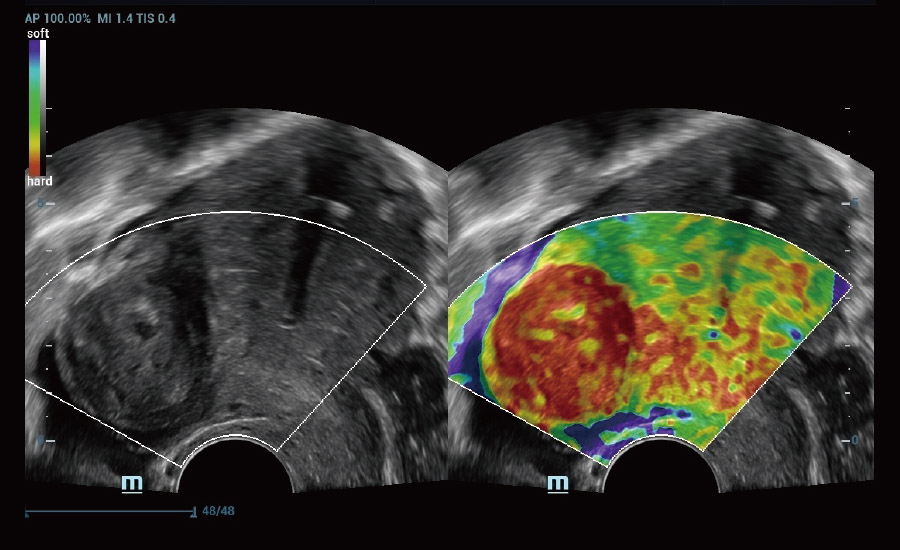

Explore mais detalhes e realidade escondida

UMA (angiografia ultramicroscĆ³pica)

A tecnologia inovadora elimina as limita??es das tradicionais imagens com Doppler. Com resolu??o espacial e sensibilidade de fluxo ultra-altas, permite a detec??o de perfus?es de fluxos muito sutis e lentos, ampliando assim a aplica??o clĆnica da avalia??o qualitativa e quantitativa do ultrassom no cĆ©rebro fetal, rins, placentas, endomĆ©trios, ovĆ”rios etc.